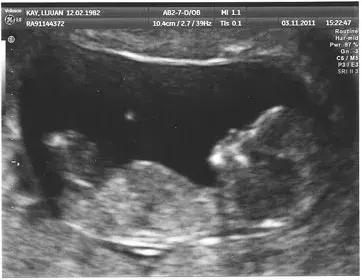

胎儿超声检查更是超声检查的独有优势,20年前大家还不太能接受超声胎儿检查,担心对孩子有影响,不过现在大家都有了超声孕检的观念,在孕期中孕大排畸检查(三级筛查)已经广为大家所接受,对国家优生优孕有重大的促进作用。不过早中孕系统筛查也非常重要,而目前仍未被大家所重视。

提示:早中孕期胎儿超声筛查是十分有必要的。

许多严重的胎儿畸形,如单心室、心室发育不良、心内膜垫缺损等,都可以在早中孕周被筛查出来,所以早中孕的检查非常重要。但仍需要有一定的技巧和技术依赖性,目前仍掌握在少数高水平超声医生手上。